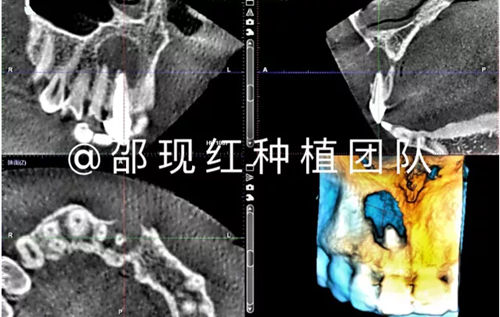

植骨術(shù)后9個月成骨情況

「科普篇」你真的了解它嗎?——β-磷酸三鈣